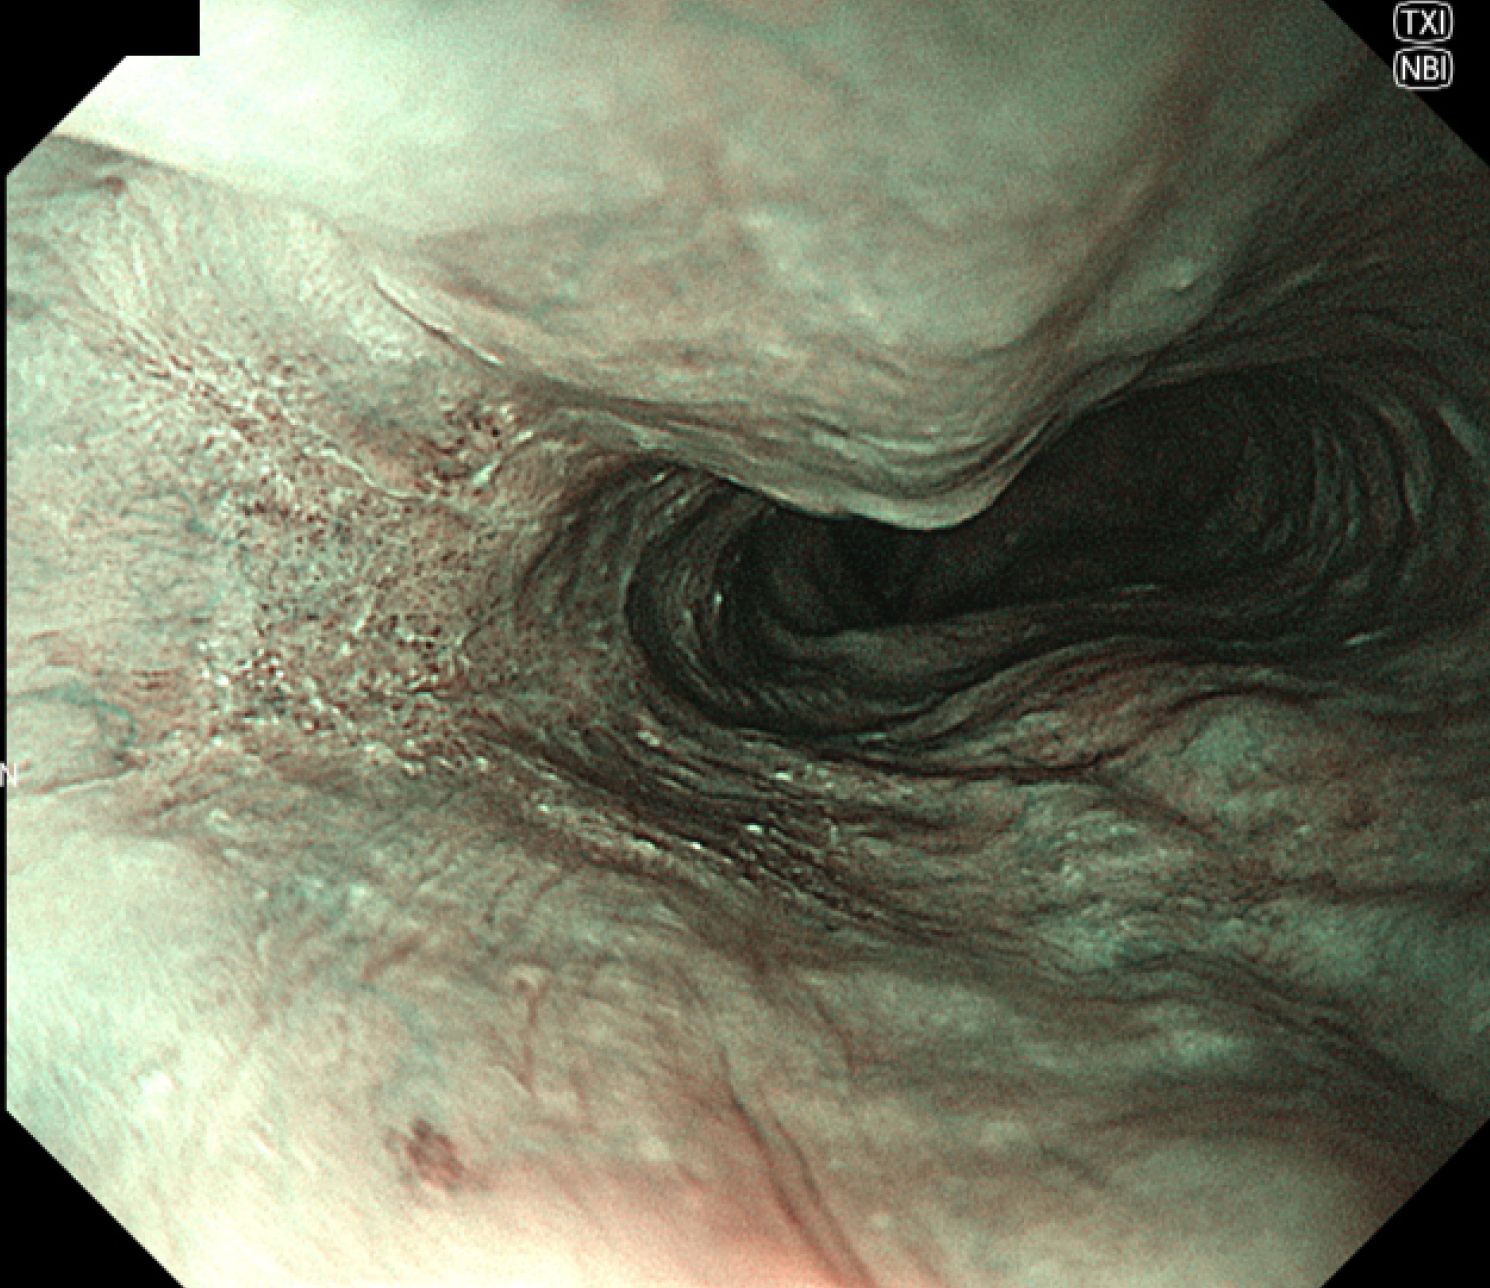

• 白色光観察①(中遠景)

強調設定:A5

図1 WLI 食道病変

白色光非拡大観察では画面全体にピントがあった画像であり、鮮明な印象である。食道左壁に周囲正常粘膜と比較してやや粗造な粘膜を認める。